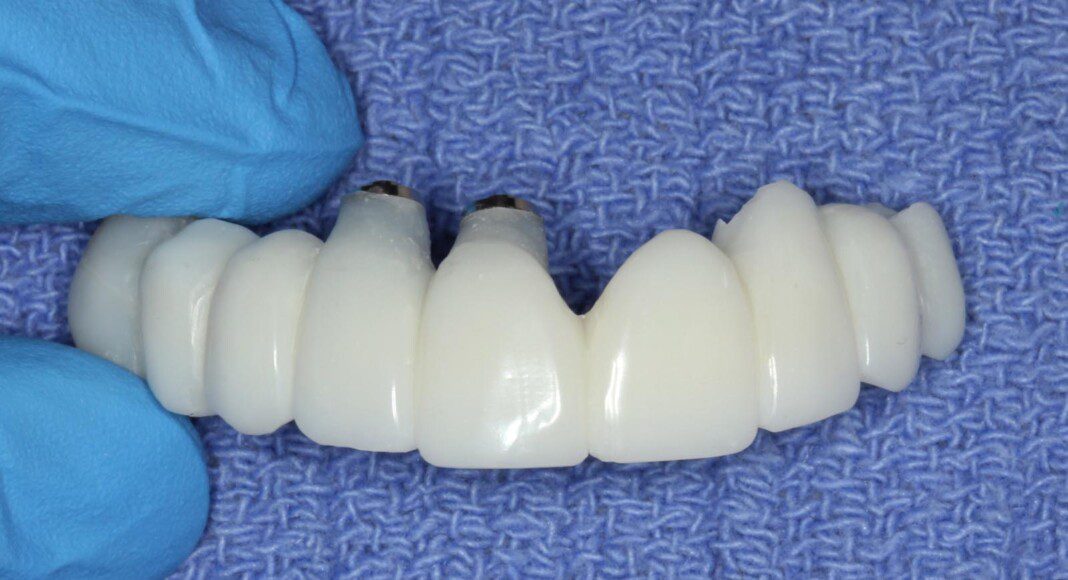

Zirconia bridge cemented to the titanium cylinders (tissue view) + one cemented unit on one old implant. The angle of this implant was too far forward. By cementing this one, we can still use it for retention and stability. Note the convex nature of the tissue interface for easy cleaning.